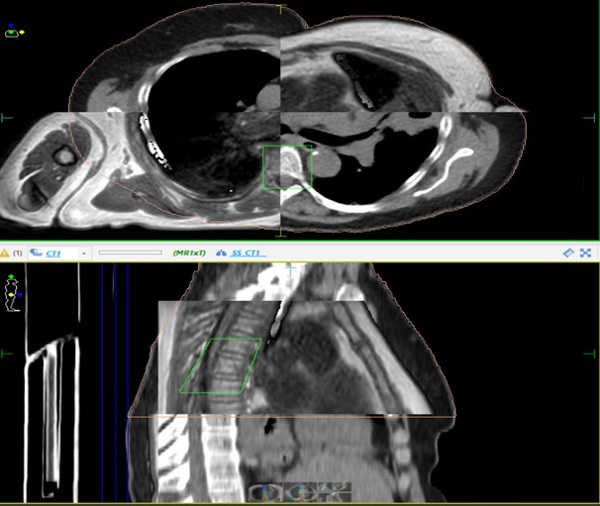

(This project explored barriers patients face when considering participation in radiotherapy trials, with the goal of improving recruitment and equity in access) - Alice Greenwood-Wilson – MR-only workflow for MSCC patients: Exploring the potential of CT-free planning on the MR-Linac

(This study assessed the feasibility of using MR-only imaging to plan treatment for metastatic spinal cord compression (MSCC), reducing the need for multiple imaging appointments) - Claire Nelder – Evaluation of the dosimetric impact of bladder variability on a cervical cancer cohort